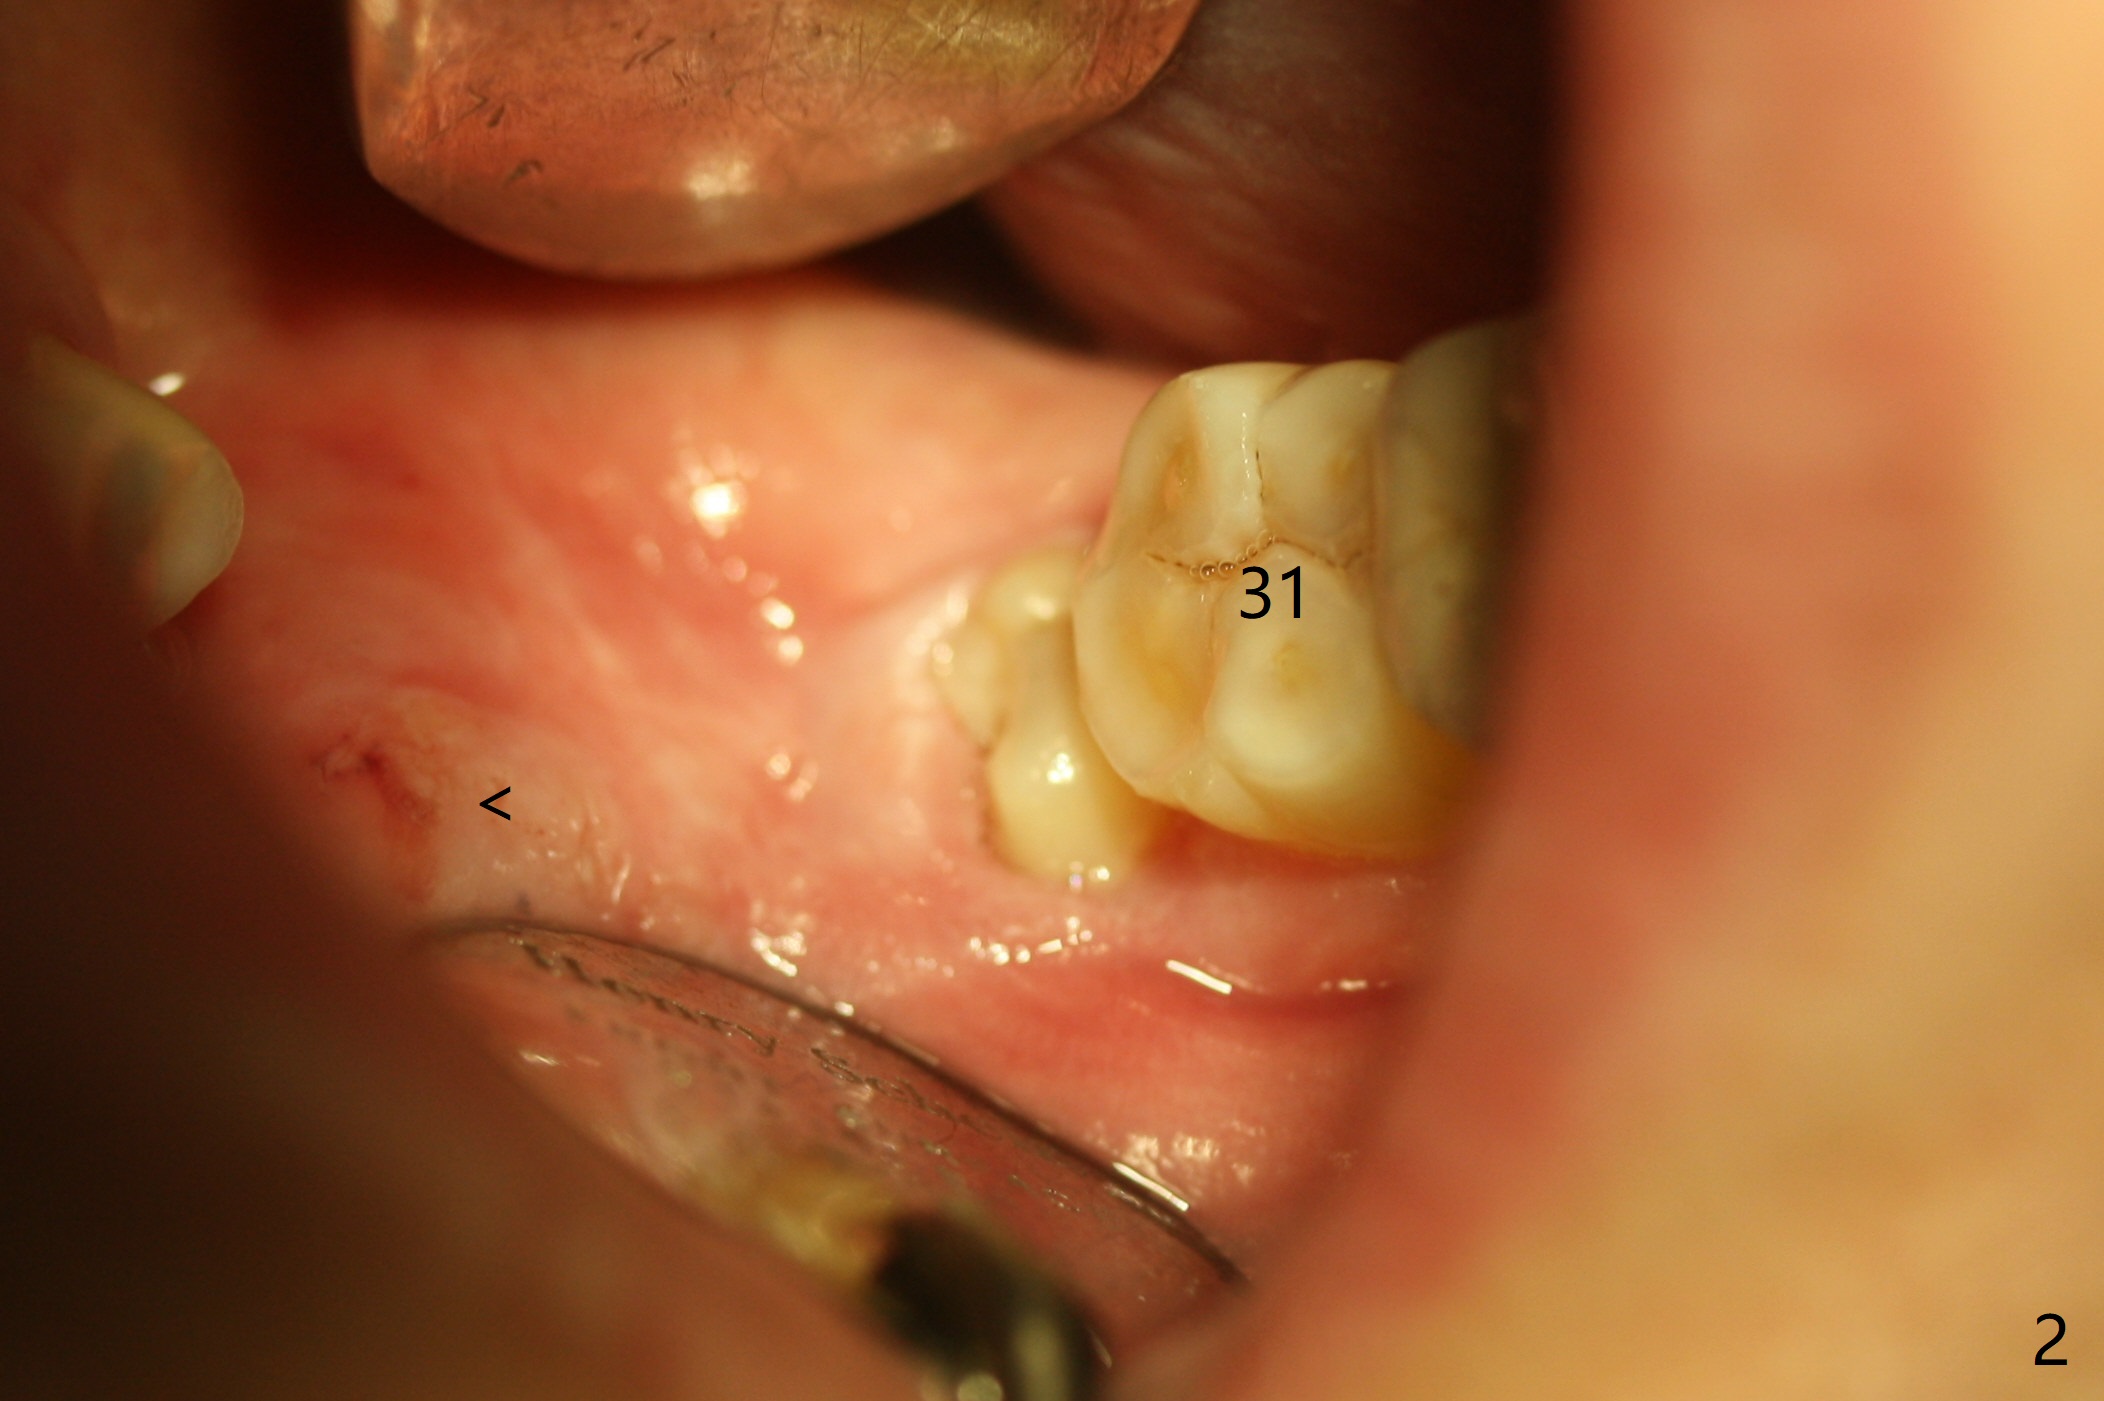

A 37-year-old woman requests extraction of the tooth #32 (Fig.1,2 (< cheek bite)). Note no bone between the last 2 molars. The tooth is extracted with incision, but without bone removal. Vanilla graft (Fig.3 *) is placed as mesial as possible, while Osteogen plug (P) coronal before suturing. The white dashed line in Fig.4 most likely represents the mesial wall of the 3rd molar socket (fused roots). The distal root of the 2nd molar seems to be partially covered by the bone.